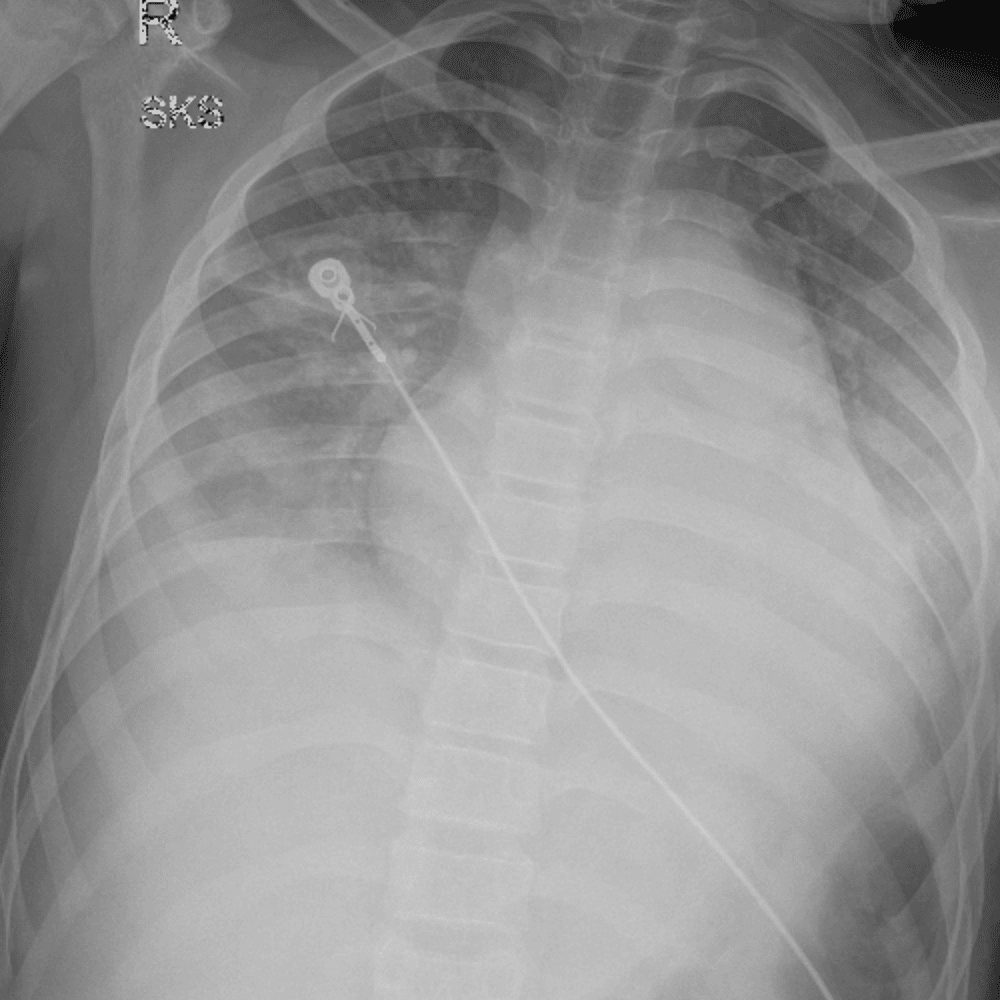

Peds Chest

Practice

Simulates call by including subtle or difficult cases and some normals.

50 cases